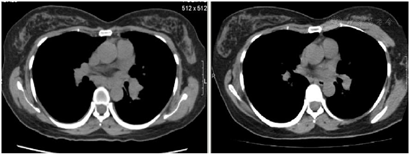

经积极抗感染及对症治疗,患者症状好转,右侧颈部及锁骨上肿大淋巴结缩小。胸部CT提示肺门、纵隔淋巴结明显缩小。

患者,女性,47岁,因发现多发淋巴结肿大2年余,于2022年1月14日入院。患者缘于2年余前发现右侧锁骨上多个淋巴结肿大,最大大小约2 cm×2 cm,质稍硬,伴疼痛,活动度可,无伴发热、畏寒,无咳嗽、咳痰,无心悸、胸闷等。2020年4月至外院查胸部CT发现纵隔内气管前、隆突下、右侧肺门内见多个淋巴结影,当时未予处理。2021年7月2日于外院行右侧锁骨上淋巴结活检,病理提示慢性化脓性炎症。曾于2021年7月8日考虑风湿结缔组织病可能,予甲强龙治疗,同时于2021年8月检测抗IFN-γ抗体滴度高于1:100,考虑诊断抗干扰素γ自身抗体综合征。其后出现右侧颈部淋巴结肿大,且右侧锁骨上淋巴结明显较前增大,表面皮肤红肿,2021年8月12日于外院予行右侧锁骨上淋巴结脓液穿刺送检,脓液高通量测序提示马尔尼菲蓝状菌感染,序列5149。于2021年8月13日开始予威凡抗真菌治疗,但患者右侧颈部淋巴结未见缩小。后于2021年12月21日外院再行右侧颈部淋巴结活检,病理考虑符合特殊病原体感染,高通量宏基因测序提示波斯分枝杆菌序列352。遂转至我院就诊。查体:右侧颈部、锁骨上可触及多个淋巴结肿大,最大大小约3 cm×2 cm,质硬,活动度可,有轻压痛,无红肿、破溃、流脓,边界清。双肺呼吸音清,未闻及干湿性啰音。

实验室提示白细胞(WBC)16.33×109/L,中性粒细胞比率(NE%)76.7 %,血红蛋白(HGB) 105 g/L,嗜酸性粒性粒细胞0.89×109/L。抗IFN-γ抗体滴度治疗期间三次复查均高于1:100。血T-SPOT试验结果为不确定。HIV(-)。痰涂片找分枝杆菌×3次阴性。右侧颈部淋巴结活检病理高通量宏基因测序检测见波斯分枝杆菌属,序列数352;痰及右侧颈部淋巴结活检组织培养及鉴定提示堪萨斯分枝杆菌生长;右侧锁骨上淋巴结脓液病理高通量测序检测见马尔尼菲蓝状菌感染,序列5149;支冲液高通量测序检测见马尔尼菲蓝状菌,序列1。2022年1月19日右侧颈部淋巴结病理提示其内见胶原纤维及纤维母细胞增生,个别可疑形成不良的上皮样细胞、组织细胞、中性粒细胞、淋巴细胞及浆细胞浸润。抗酸染色见个别阳性杆菌,六胺银、Warthin-Starry及PAS染色(-)(图1)。双侧颈部淋巴结彩色超声(图2、图3);胸部CT(图4、5)。

患者于入院后22 d出院,其后规范服药,2个月后复查痰、支冲液及右侧颈部淋巴结穿刺组织培养分枝杆菌、真菌、致病菌均阴性。4个月后追踪复查彩超、胸部CT提示右侧颈部、锁骨上、纵隔淋巴结均好转、缩小。